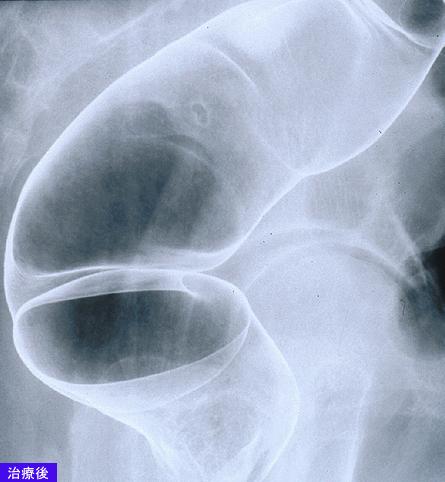

A case of MLP (multiple Lymphomatous Polyposis) type malignant lymphoma which involved the G1 tract including the esophagus.

Malignant Lymphoma/MLP type

Location

Large intestine(Colon)/Rectum

Technique, Method

X-ray